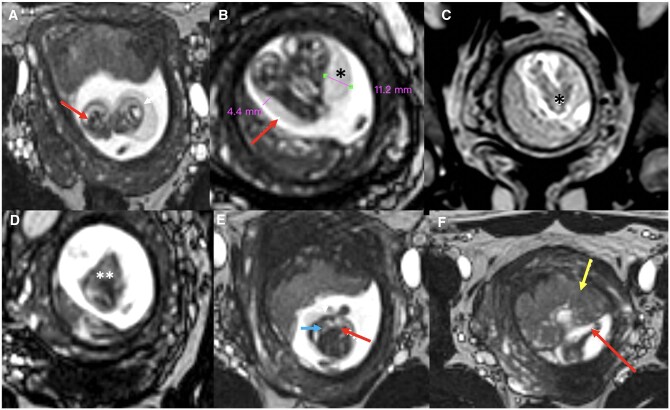

Conjoined twins, or Siamese twins as they are commonly called, are a rare and extreme form of monochorionic twinning. Imaging plays an essential role in the diagnosis and follow-up of conjoined twins. While ultrasound is often the screening modality of choice, MRI is carried out for better anatomical delineation and further characterization as and when necessary. We present a unique case of first trimester thoraco-omphalopagus conjoined twins with cystic hygroma who were comprehensively evaluated with sonography and MRI with imaging findings confirmed post-pregnancy termination. The case stresses upon the utility of advanced imaging techniques including foetal MRI that immensely contribute towards a reliable diagnosis.